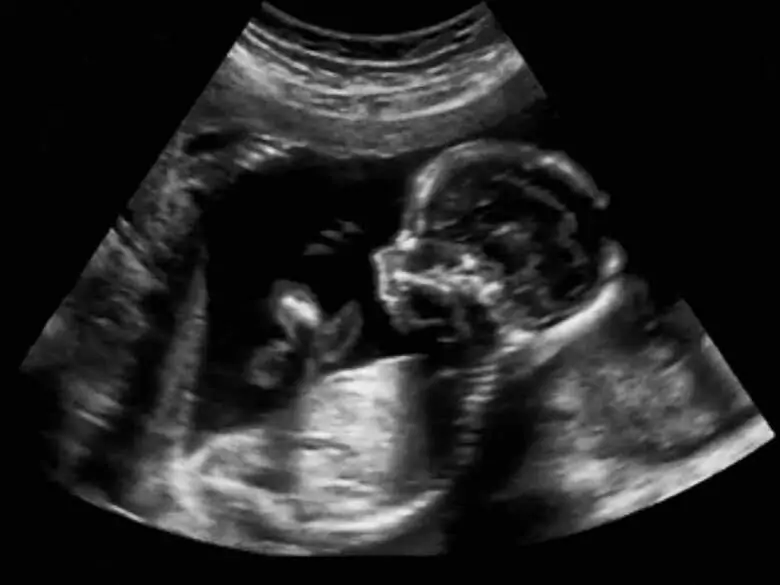

Ograniczenie wzrastania płodu rozpoznaje się, gdy dwukrotnie wykonany pomiar wskazuje zbyt wolne wzrastanie płodu - gdy masa i długość ciała jest poniżej wyznaczonej normy. Częstość występowania IUGR wynosi około 3-10% noworodków żywo urodzonych.